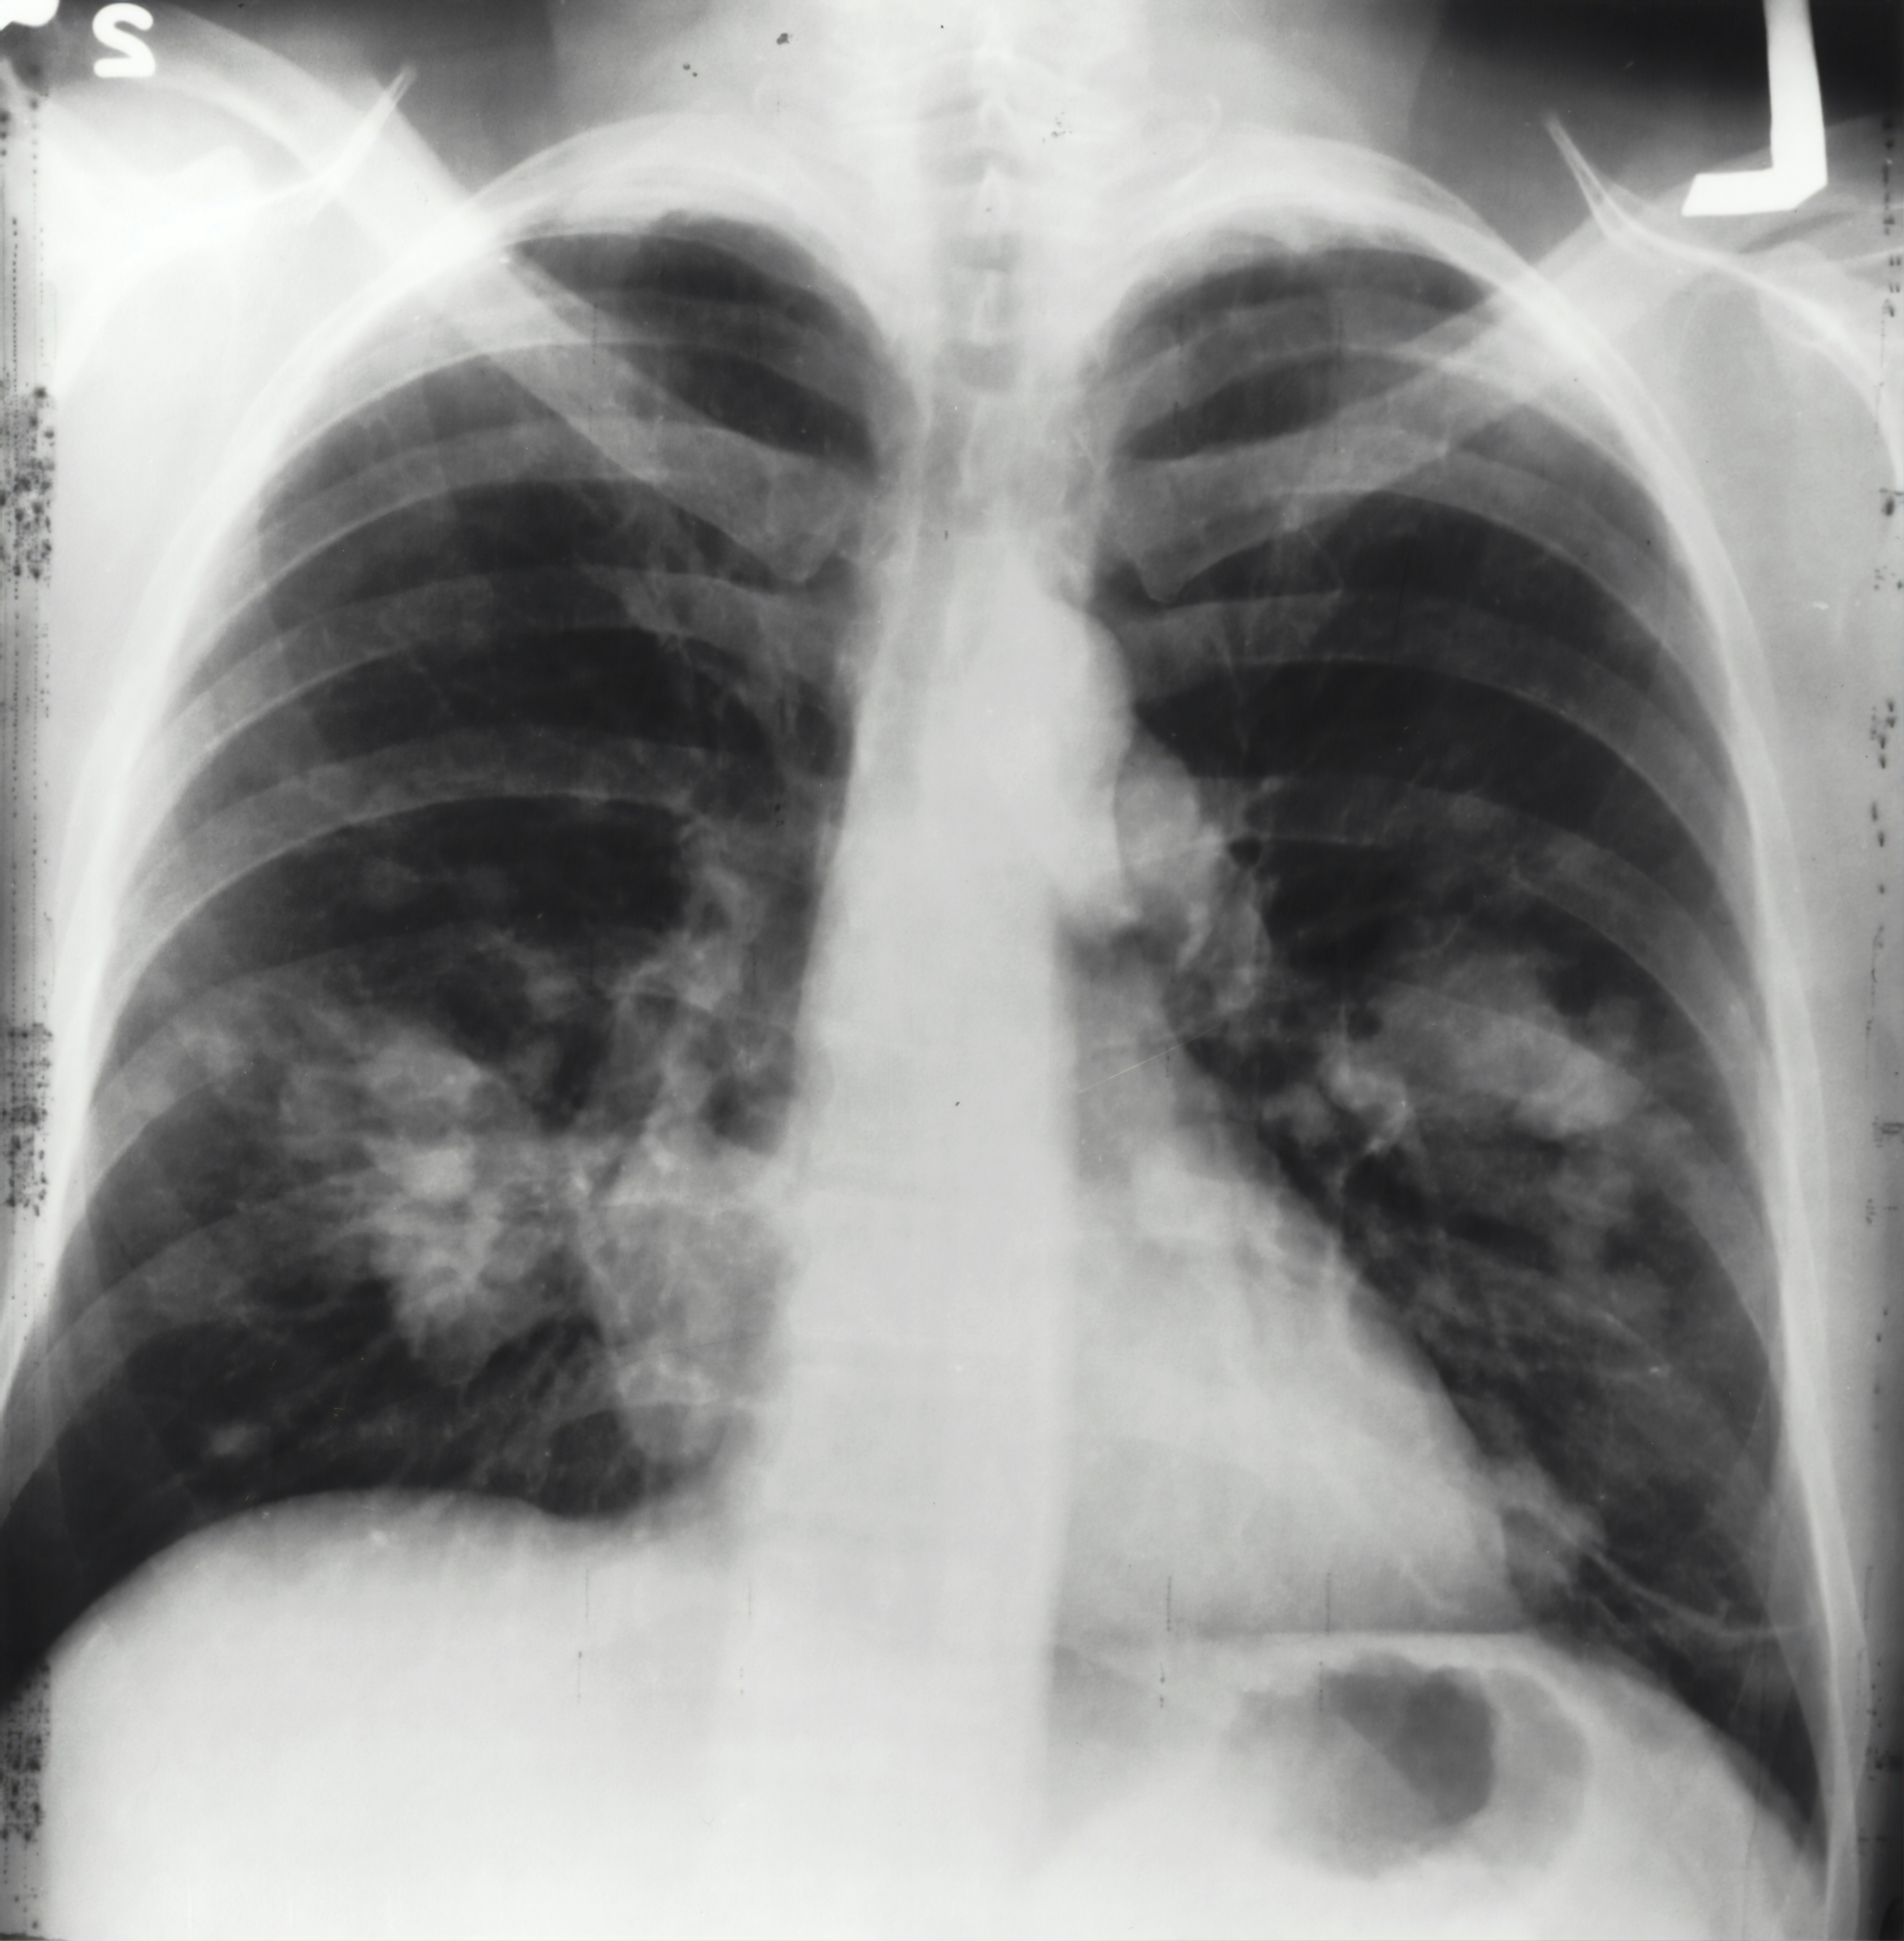

기관지염과 폐렴은 호흡기의 일부에 위치한 질환으로서 서로 연관성이 있을 수 있습니다. 기관지염은 기관지의 염증으로 인한 질환으로써 주로 기침, 가래, 호흡 곤란 등의 반응이 생기고 폐렴은 폐의 세포에 염증이 발생하는 질환으로 기관지염과 비슷한 증상들이 발생합니다.